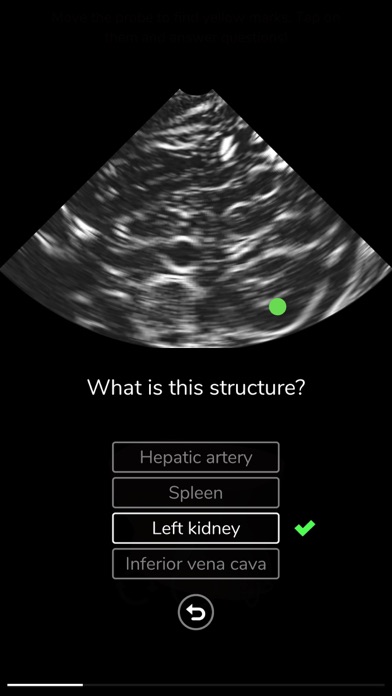

Learn ultrasound in a virtual ultrasound simulator. Deepscope ultrasound virtual learning modules are created to help learn the techniques of ultrasound.

-Challenges